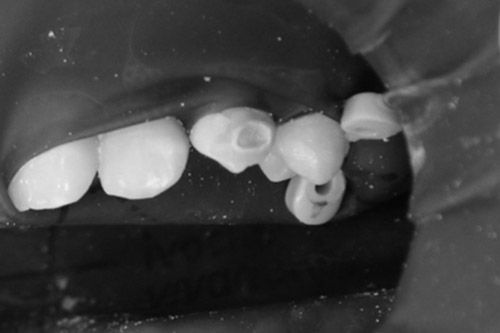

Paciente femenino de 15 años de edad que presenta una hipomineralización incisivo molar (HIM) de grado moderada código 2 y caries incipiente en el O.D. 23 en la cara vestibular. Se encuentra aparentemente sana sistémicamente.